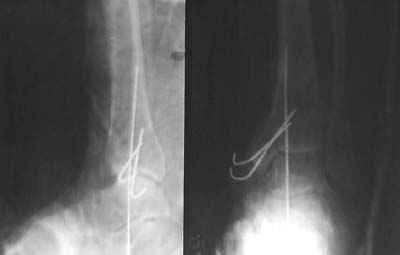

После совместного осмотра с зав.отд.микрохирургии пациент госпитализирован в клинику микрохирургии. Дежурными врачами этой же клиники принято решение сохранить конечность, выполнены ПХО, фиксация спицами, гипсовая иммобилизация. Результаты - см.приложение.

А что с малоберцовой костью? Как Вы классифицировали данный перелом и повреждение мягких тканей?